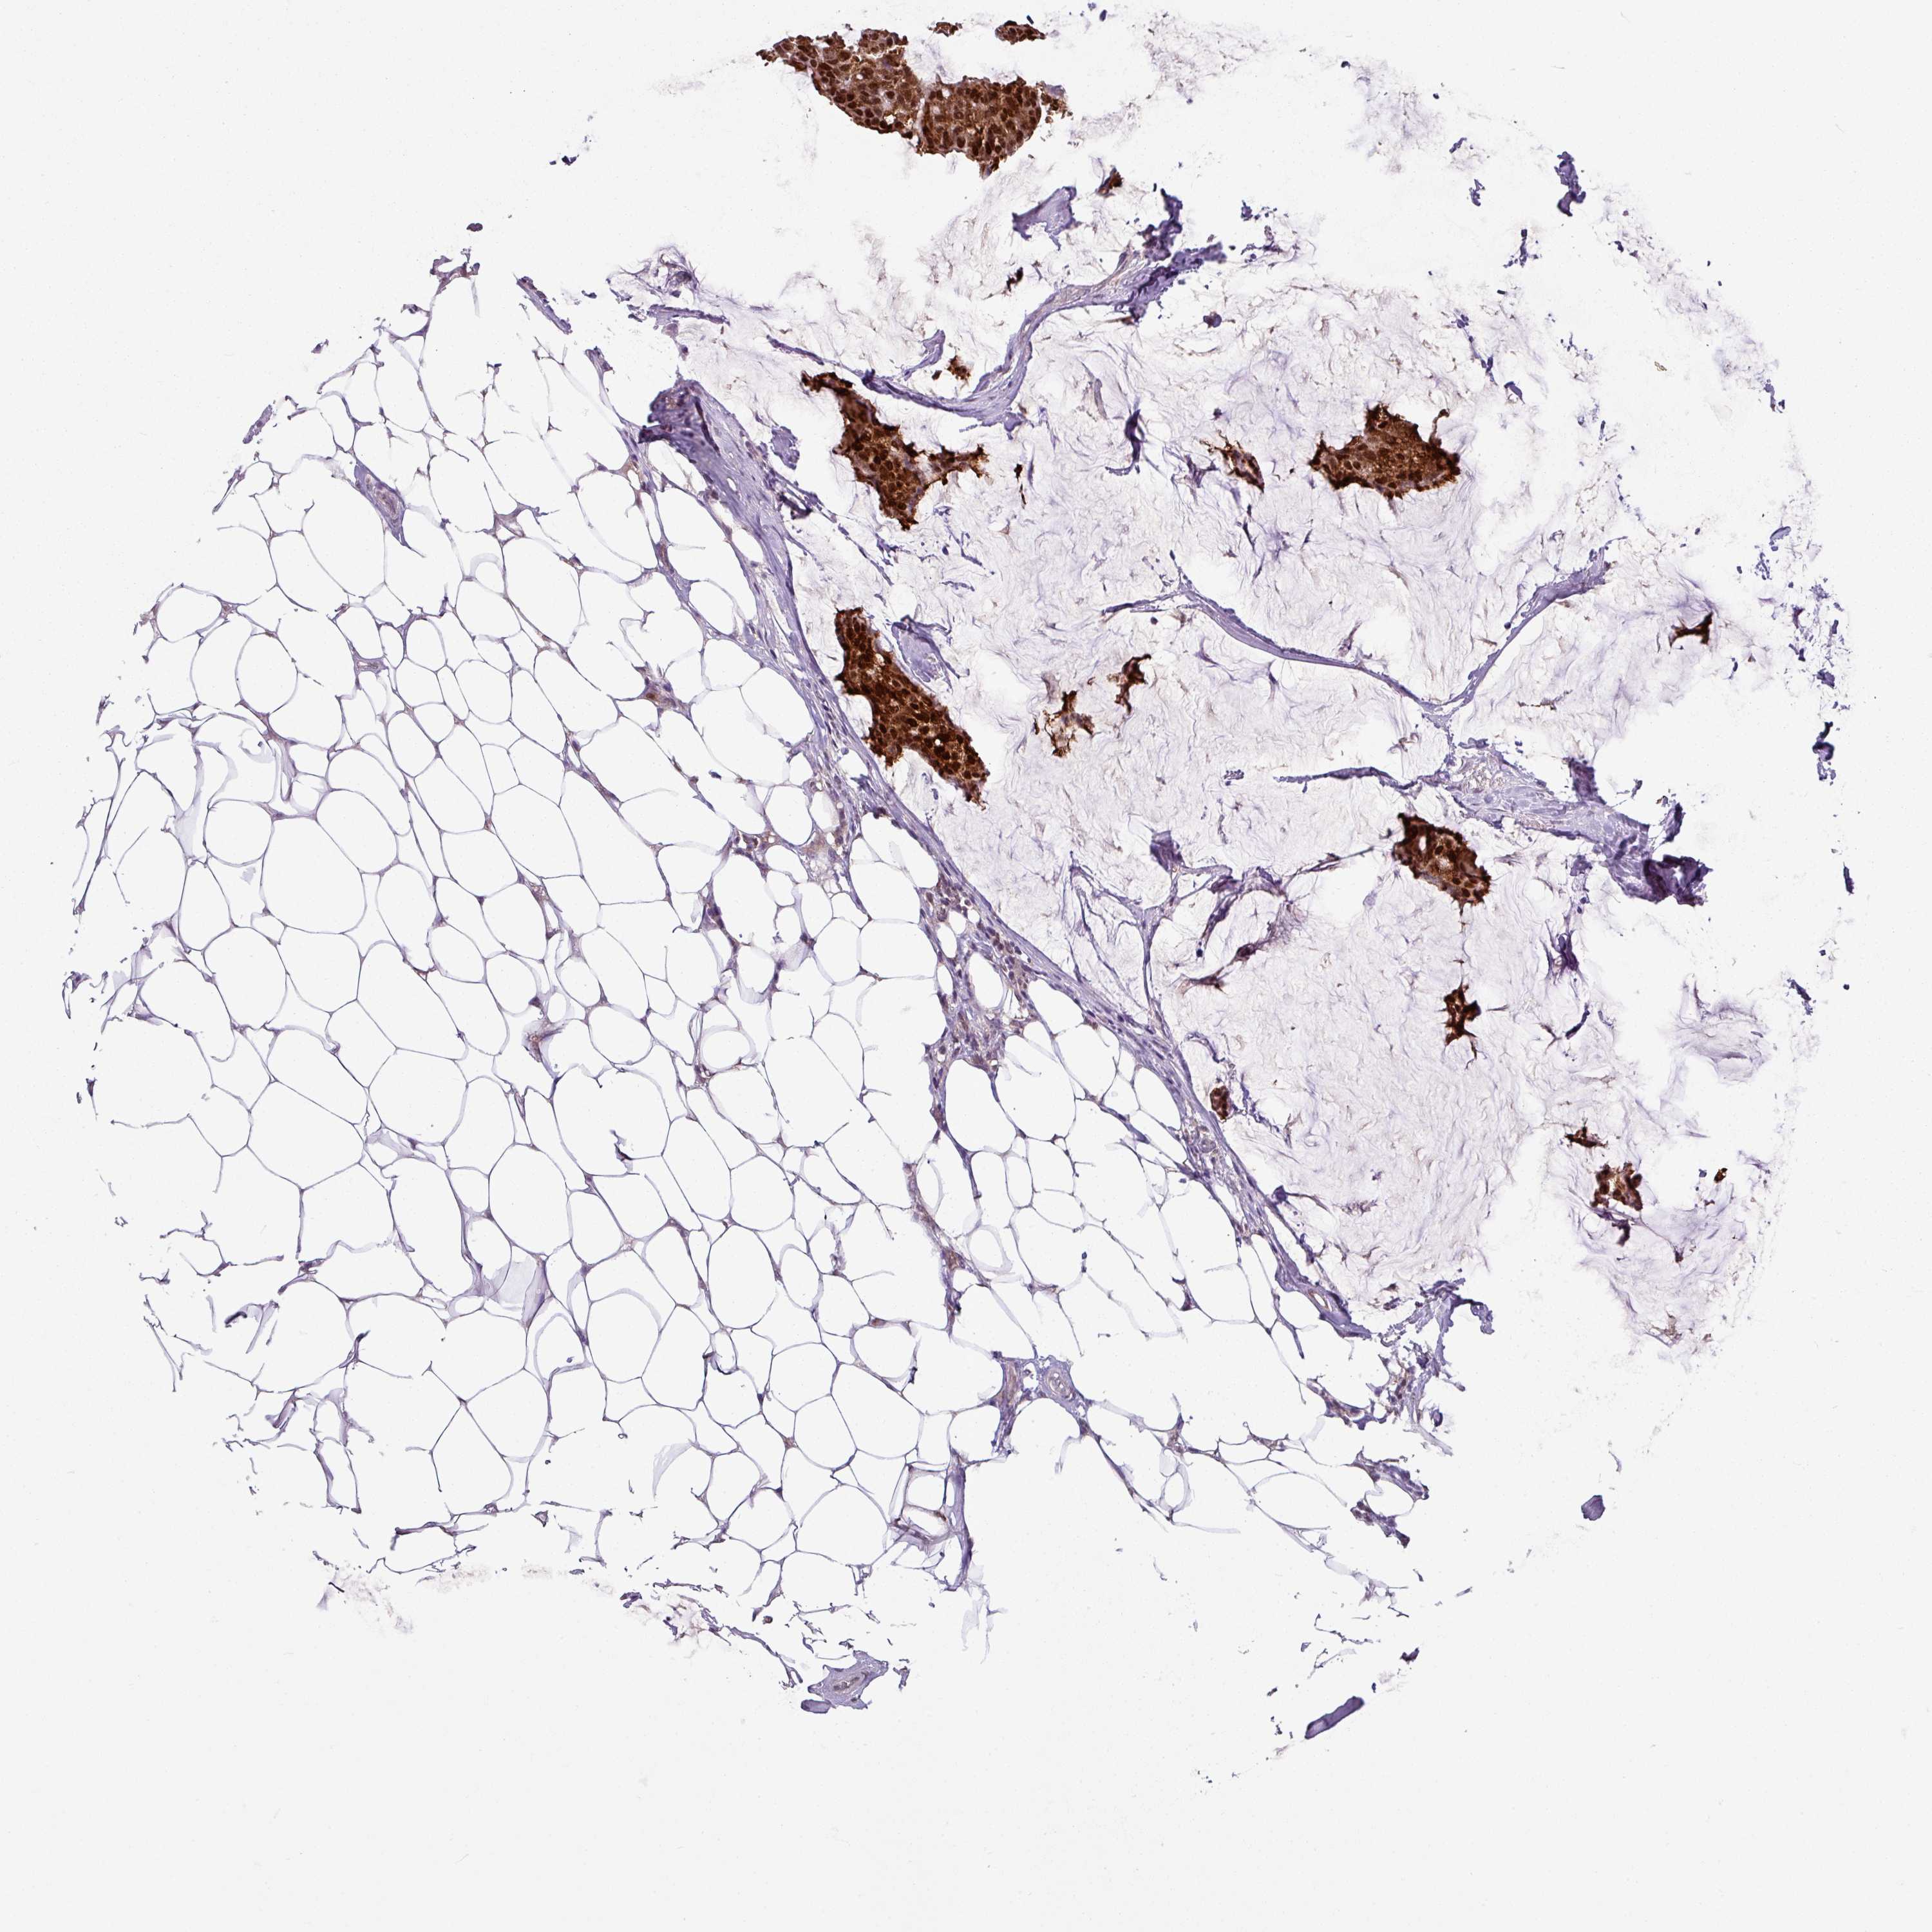

CANCER BREAST CANCER Show tissue menu

BRCA TCGA BRCA VALIDATION PROTEIN EXPRESSION